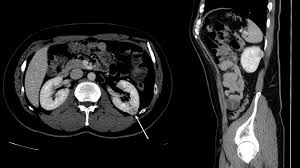

신장은 인체의 대사 노폐물을 제거하고 수분 및 전해질 균형을 유지하는 중요한 역할을 합니다. 신장에 문제가 발생하면 체내의 여러 기능이 부정적인 영향을 받을 수 있습니다. 복부 CT는 신장 결석, 신장 종양 및 기타 신장 관련 질환을 진단하는 데 도움을 줍니다.

신장 결석: 예방법과 치료 방법

신장 결석은 신장에서 형성된 경결된 물질로, 통증을 유발할 수 있습니다. 복부 CT는 결석의 위치와 크기를 정확하게 파악할 수 있으며, 이 정보를 바탕으로 적절한 치료 방법을 결정하는 데 매우 중요합니다. 결석이 발견되면, 물리치료, 약물 치료, 혹은 필요 시 수술이 고려될 수 있습니다. 신장 결석은 수분 보충과 균형 잡힌 식사를 통해 예방할 수 있으므로, 생활 방식의 변화 또한 동반되어야 합니다.